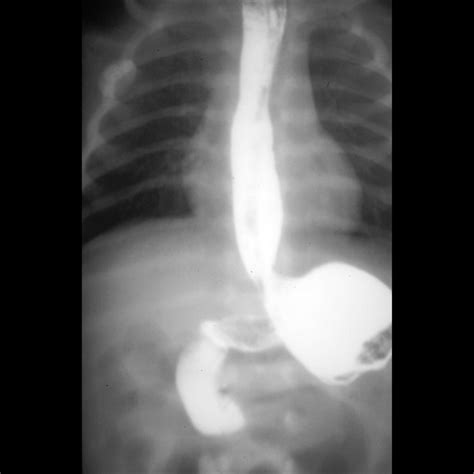

• Upper GI Series: A test where a contrast dye is swallowed, and X-rays are taken to visualize the esophagus, stomach, and small intestine.